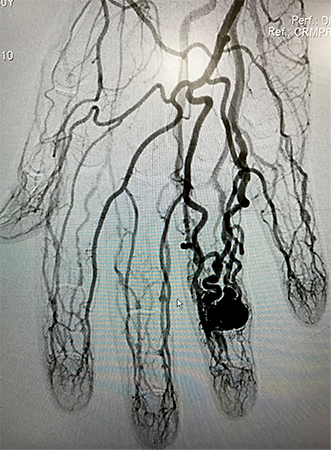

Embolização de Varizes Pélvicas

Varizes Pélvicas é o nome dado para a dilatação das veias localizadas no interior da pelve, próximas ao útero, bexiga e reto. Quando volumosas, essas varizes provocam dor no baixo ventre, dor durante a relação sexual, hemorroidas e varizes na face interna da coxa e períneo. Novas técnicas endovasculares pouco invasivas, permitem o tratamento do problema, com melhora na qualidade de vida desses pacientes.

A embolização de varizes pélvicas é feita através da punção de uma veia superficial do braço. Utilizando cateteres, o cirurgião vascular ocluirá os vasos doentes com liberação de espirais metálicas e substância química na forma de microespuma densa.

As molas em conjunto com a espuma provocarão a oclusão gradual das veias que originam as varizes, levando ao seu desaparecimento.